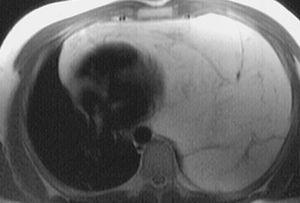

La tomografía computarizada puso de manifiesto una masa de 20 x 21 x 18 cm, que ocupaba la totalidad del hemitórax izquierdo, desplazaba el mediastino hacia el lado contralateral y colapsaba el pulmón hacia la zona más superior de este hemitórax. No se observaban signos de infiltración en las estructuras vecinas. En la resonancia magnética la tumoración brillaba en secuencias ponderadas en T1, era isointensa con la grasa y anulaba su señal en secuencias de saturación grasa (fig. 1).

Fig. 1. Resonancia magnética torácica, donde se observa una gran masa torácica izquierda de densidad grasa que ocupa toda la cavidad pleural y el mediastino anterior con colapso pulmonar completo.

En la radiografía simple, no es infrecuente que se pueda confundir con una cardiomegalia, como ocurrió en nuestro caso9. El diagnóstico diferencial hay que realizarlo principalmente con el lipoma, la hiperplasia tímica y el liposarcoma, por lo que es necesaria la realización de tomografía axial computarizada o resonancia magnética de tórax. En la resonancia magnética secuencia-T1, el tejido graso tumoral aparece atenuado y en secuencia-T2 la grasa presenta baja atenuación y los restos tímicos aparecen brillantes.